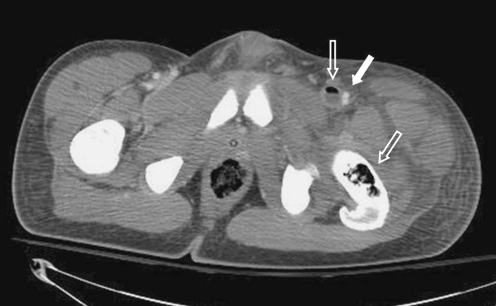

After intravenous fluid rehydration, the patient’s creatinine improved to 1.2 mg/dl, and a contrast CT scan of the chest, abdomen, pelvis, and left lower extremity was obtained. Chest CT was negative for PE, but demonstrated diffuse hazy opacification of both lungs with air bronchograms, consistent with ARDS. CT of the left lower extremity demonstrated thrombus and air within the left common femoral vein with fluid throughout the myofascial planes of the left thigh and air within the left femur consistent with osteomyelitis (Fig. 4). Repeat duplex ultrasound of the left lower extremity confirmed thrombus in the left common femoral vein. An inferior vena cava filter was placed to prevent embolization of septic thrombi. The patient subsequently became hypotensive with increasing respiratory distress, requiring inotropic support and mechanical ventilation lasting several days.

Fig. 4.

CT scan of abdomen and pelvis with contrast demonstrating clot (white arrow) and air (gray arrow) within the left common femoral vein and within the left femur consistent with osteomyelitis. Fluid throughout the myofascial planes of the left thigh is also seen; 340×96 mm (96×96 DPI)